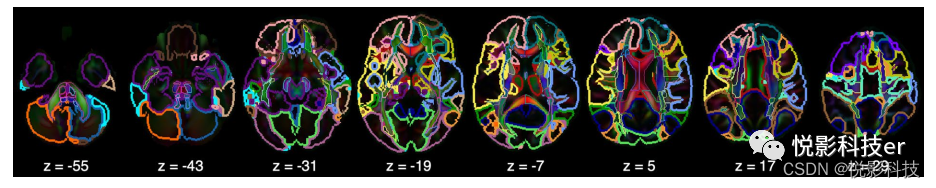

谱聚类算法从rs-fMRI数据中识别出22个功能网络。图5a展示了轮廓系数,表明轮廓系数在大脑被分为22个功能网络时达到最大值。目测舍弃2个主要位于脑白质和脑脊液的功能网络,得到最后20个功能网络。图4展示了大脑轴向图上的20个功能网络,图6提供了每个网络的三视图。20种功能网络的描述信息如表S2所示。

图4 静息态功能图集